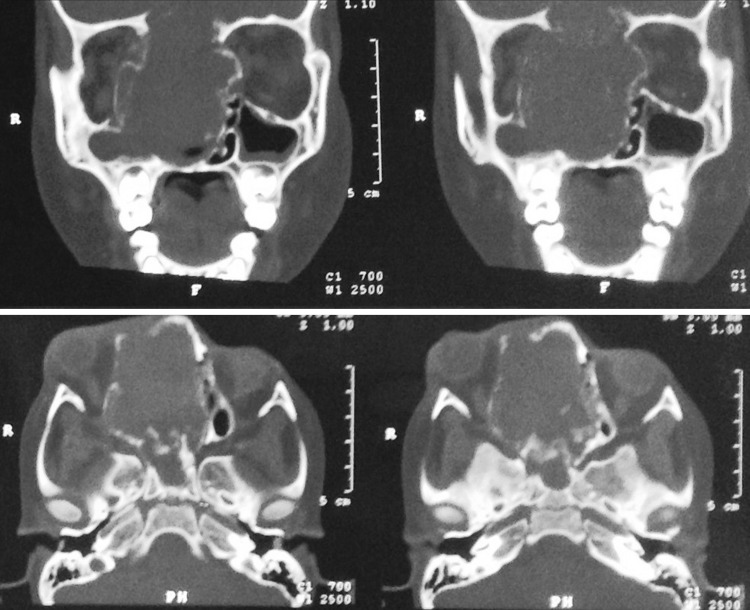

Fig. 4.

Case 2—coronal CT scan 6 months after final surgery showing no evidence of residue/recurrence of lesion